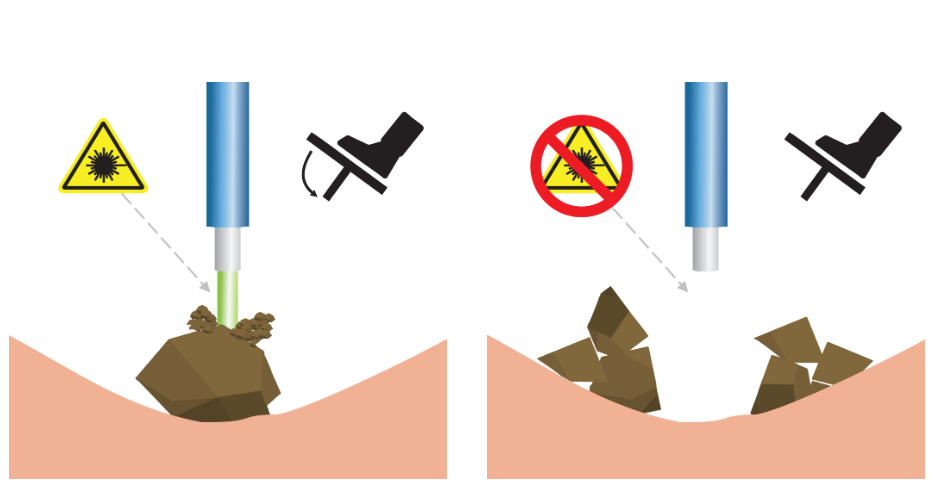

Функция "Детектор ткани"

"Детектор ткани" - это инновационная разработка, направленная на абсолютную максимизацию безопасности во время дробления камней. Технология особенно полезна при эндоскопическом лечении мочекаменной болезни.

Благодаря технологии детектирования тканей лазер различает какая ткань (твердая или мягкая) находится перед торцом хирургического волокна. Таким образом, при проведении литотрипсии, лазер автоматически останавливает подачу излучения при наведении на слизистую, тем самым повышая безопасность операции.

Технология позволяет уменьшить риск попадания лазерного излучения на окружающие мягкие ткани во время дробления камней и снизить нагрев окружающей жидкости вследствие “непродуктивных” импульсов, не достигших цели.

Демонстрация работы технологии

-

Перкутанная нефролитотрипсия.

-

Волокно 550 нм. Плотность = 1640 HU. Параметры: 3 Дж x 13 Гц = 39 Вт

-

Педаль нажата постоянно. Зеленый сигнал демонстрирует наличие излучения. Красный сигнал - его отсутствие.

Датчик ткани — это инновационная разработка «ИРЭ-Полюс», направленная на абсолютную максимизацию безопасности во время дробления камней. Данная технология призвана усилить развивающийся тренд на эндоскопическое лечение мочекаменной болезни.Принцип работы Tissue sensor заключается в том, что лазер различает какая ткань (твердая или мягкая) находится перед торцом хирургического волокна. Таким образом, при проведении литотрипсии, лазер автоматически останавливает подачу излучения при наведении на слизистую, исключая риск повреждения.

Tissue sensor позволяет достичь высокого уровня безопасности эндоскопического лечения мочекаменной болезни, снижается травматизация тканей во время литотрипсии.

Настройка чувствительности имеет несколько уровней. Это позволяет получить максимально корректное распознавание камней и мягких тканей даже в сложных условиях, например, при плохой видимости, плохом оттоке ирригационной жидкости, повышенной «пыльности» камня, при фрагментации в режиме «попкорнинга» или если дробление с прямым контактом камня и волокна невозможно.

В лазере UROLASE MAX функция «Детектор ткани» установлена и доступна к работе сразу после ввода лазера в эксплуатацию.